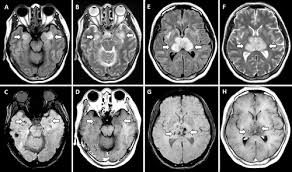

Two subtypes are recognized which differ in demographics, virus, and pattern of involvement. Become a gold supporter and see no ads. Bilateral temporal lobe t2 hyperintensity refers to hyperintense signal involving the temporal lobes on t2 weighted and flair imaging. Hypertrophic pachymeningitis is a condition where there is localized inflammatory thickening of the dura. Limbic encephalitis, mca ischaemia, tumours, effects of seizures) hyperintense t2 signal in the medial temporal lobes, inferior frontal lobes and insula basal ganglia are usually spared Reference osborn a, et al. Given the history of fever and seizures coupled with the mri findings of bilateral mesial temporal lobe changes, herpes encephalitis requires clinical consideration. The changes spare the basal ganglia, a feature which is helpful in distinguishing an mca infarct with hemorrhagic transformation from herpes simplex encephalitis, the diagnosis in this case. Mri demonstrates extensive edema in the right temporal lobe with areas of intrinsic high t1 signal, in keeping with hemorrhage. It is estimated to occur in ~2% of pati. The differential diagnoses include limbic encephalitis (paraneoplastic), gliomatosis cerebri, and status epilepticus. It is reasonable to obtain an mri when patients are asymptomatic to ensure that no other abnormality is present which may be causing a recurrent chemical meningitis (e.g. Axial t2 prominent swelling, increase t2 signal involving the left temporal lobe and insular cortex.

Axial t2 prominent swelling, increase t2 signal involving the left temporal lobe and insular cortex. Two subtypes are recognised which differ in demographics, virus, and pattern of involvement. Multilocularis.the larval stage is the cause of hydatid disease in humans 1. Cerebral malaria is a rare intracranial complication of a malarial infection. The changes spare the basal ganglia, a feature which is helpful in distinguishing an mca infarct with hemorrhagic transformation from herpes simplex encephalitis, the diagnosis in this case.

Mri demonstrates extensive edema in the right temporal lobe with areas of intrinsic high t1 signal, in keeping with hemorrhage. Become a gold supporter and see no ads. For a general discussion, and for links to other system specific manifestations, please refer to the article on coccidioidomycosis. This patient went on to have hsv encephalitis proven on csf pcr. This patient went on to have hsv encephalitis proven on csf pcr. Spinal hydatid disease is an uncommon manifestation of hydatid disease, caused by the larval stage of echinococcus granulosus, or less commonly e. Given the history of fever and seizures coupled with the mri findings of bilateral mesial temporal lobe changes, herpes encephalitis requires clinical consideration. Multilocularis, and describes a spectrum of disease involving the spinal cord, the spine, or both. Herpes simplex encephalitis radiology case radiopaedia mri demonstrates extensive edema in the right temporal lobe with areas of intrinsic high t1 signal, in keeping with hemorrhage. Hsv encephalitis | radiology case | radiopaedia.org. Two subtypes are recognised which differ in demographics, virus, and pattern of involvement. It is estimated to occur in ~2% of pati. Reference osborn a, et al.

Herpes simplex (hsv) encephalitis is the most common cause of fatal sporadic fulminant necrotising viral encephalitis and has characteristic imaging findings. The differential diagnoses include limbic encephalitis (paraneoplastic), gliomatosis cerebri, and status epilepticus. The basal ganglia are usually spared. Note the high signal in the caudate heads and putamen on flair. Bilateral temporal lobe t2 hyperintensity refers to hyperintense signal involving the temporal lobes on t2 weighted and flair imaging. It is reasonable to obtain an mri when patients are asymptomatic to ensure that no other abnormality is present which may be causing a recurrent chemical meningitis (e.g. For a general discussion, and for links to other system specific manifestations, please refer to the article on hydatid disease. Radiopaedia is free thanks to our supporters and advertisers.

Axial t2 prominent swelling, increase t2 signal involving the left temporal lobe and insular cortex. It is estimated to occur in ~2% of pati. Become a gold supporter and see no ads. This patient went on to have hsv encephalitis proven on csf pcr. A brain biopsy was performed and the histology was consistent with encephalitis. The differential diagnoses include limbic encephalitis (paraneoplastic), gliomatosis cerebri, and status epilepticus. Multilocularis.the larval stage is the cause of hydatid disease in humans 1. It is usually bilateral but asymmetrical. Spinal hydatid disease is an uncommon manifestation of hydatid disease, caused by the larval stage of echinococcus granulosus, or less commonly e. Limbic encephalitis, mca ischaemia, tumours, effects of seizures) hyperintense t2 signal in the medial temporal lobes, inferior frontal lobes and insula basal ganglia are usually spared It is reasonable to obtain an mri when patients are asymptomatic to ensure that no other abnormality is present which may be causing a recurrent chemical meningitis (e.g. 10 public playlist includes this case Pcr was repeated on the biopsy specimen and was positive for hsv.